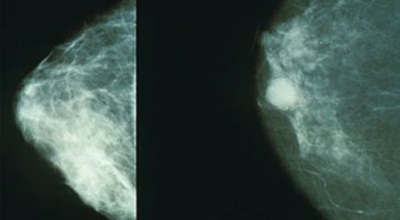

유방 밖으로 퍼진 악성 종양으로 생명을 위협할 수 있습니다. 유방암은 보통 유방의 유관과 소엽에서 발생하는데요 남성도 드물게 유방암에 걸릴 수 있습니다. 유방암은 아직 명확한 원인이 노출되지 않았습니다. 하지만 다양한 위험 요인을 추정할 수 있는데요 유전, 호르몬, 노화, 음주, 비만 등이 있어요. 가장 흔한 증상은 유방에 생기는 종괴입니다. 그리고 유두 분비, 유방통, 피부궤양, 함몰, 겨드랑이 종괴 등이 나타날 수 있습니다. 증상들이 반드시 유방암을 나타내는 것은 아닐 수도 있기 때문에 정확한 검사가 필요하다고 합니다.